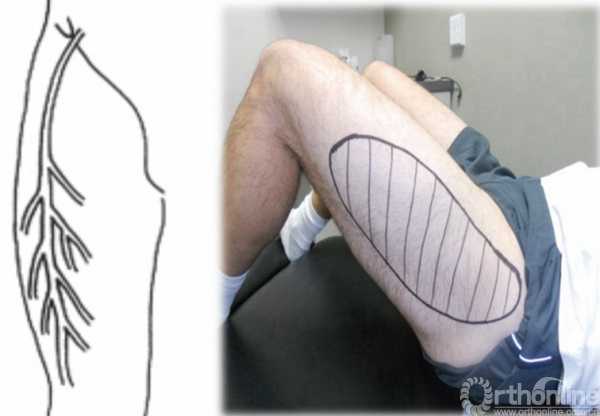

股外侧皮神经 股外侧皮神经的感觉支配区

这一类综合征便是因大腿前外侧的股外侧皮神经(lateral femoral cutaneous nerve,LFCN)腹股沟区的机械性卡压或弥漫性炎症导致的大腿前外侧皮肤感觉异常或疼痛的一系列症状。

感觉异常性股痛的主要临床表现为皮肤的麻木不适、烧灼样痛或蚁走感等,患者可能在持续站立和行走、上下车时出现疼痛,坐下时缓解。它常见于单侧下肢,而双侧较少见。其主要表现为感觉异常症状,而不会出现肌力的改变。

股外侧皮神经为何会出现损伤,那还得先从神经的解剖走行说起。股外侧皮神经源自L2-3神经前支后股,它从腰大肌外缘向下经髂肌前跨过髂窝,近似直角转折进入髂前上棘内侧腹股沟韧带下的纤维性管道内。之后出纤维管道后行于大腿阔筋膜深部,于髂前上棘下方3.0~5.0 cm处穿出阔筋膜。而股外侧皮神经在纤维管道内和股部阔筋膜穿出点的神经干相对固定,容易受到牵张、挤压和摩擦后发生损害。